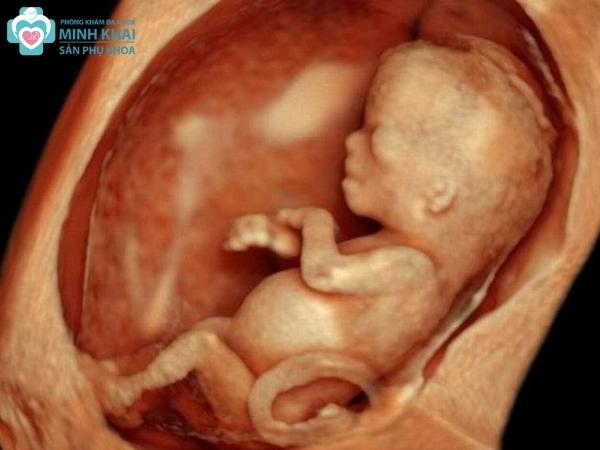

Siêu âm 5D TPHCM hay siêu âm thai 5D là kỹ thuật chẩn đoán hình ảnh hiện đại, sử dụng sóng siêu âm để tái tạo hình ảnh động của thai nhi bên trong tử cung người mẹ. Với phương pháp siêu âm 5D , mẹ bầu có thể lưu trữ, quan sát những hình thái, chuyển động và thậm chí là biểu cảm dù nhỏ nhất của con với hình ảnh rõ nét, chân thực. Không chỉ vậy, siêu âm màu 5D giúp bác sĩ phát hiện sớm các dị tật của em bé ngay từ giai đoạn đầu tiên của thai kỳ.

Hình ảnh siêu âm 5D có độ phân giải cao và có thêm màu sắc sống động. Nó giống như thước phim ngắn thể hiện được trọn vẹn sự vận động, trạng thái cũng như biểu cảm của thai nhi trong bụng mẹ một cách chi tiết nhất.

Với siêu âm thai 5D, các hoạt động và cử chỉ của thai nhi sẽ được hiển thị một cách chi tiết ngay trong thời gian thực. Ba mẹ gần như sẽ được quan sát bé qua thước phim màu ngắn để nắm trọn từng khoảnh khắc của bé con. Ngoài ra, các mặt cắt hình ảnh không gian đa chiều này còn hỗ trợ bác sĩ chẩn đoán chính xác được các bất thường của thai nhi.